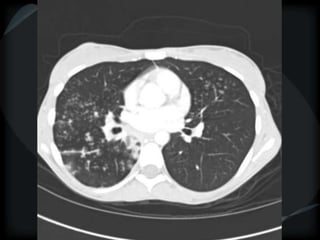

Airspace Patterns

 Inter and intralobular septal thickening / ground glass/crazy paving

Crazy paving